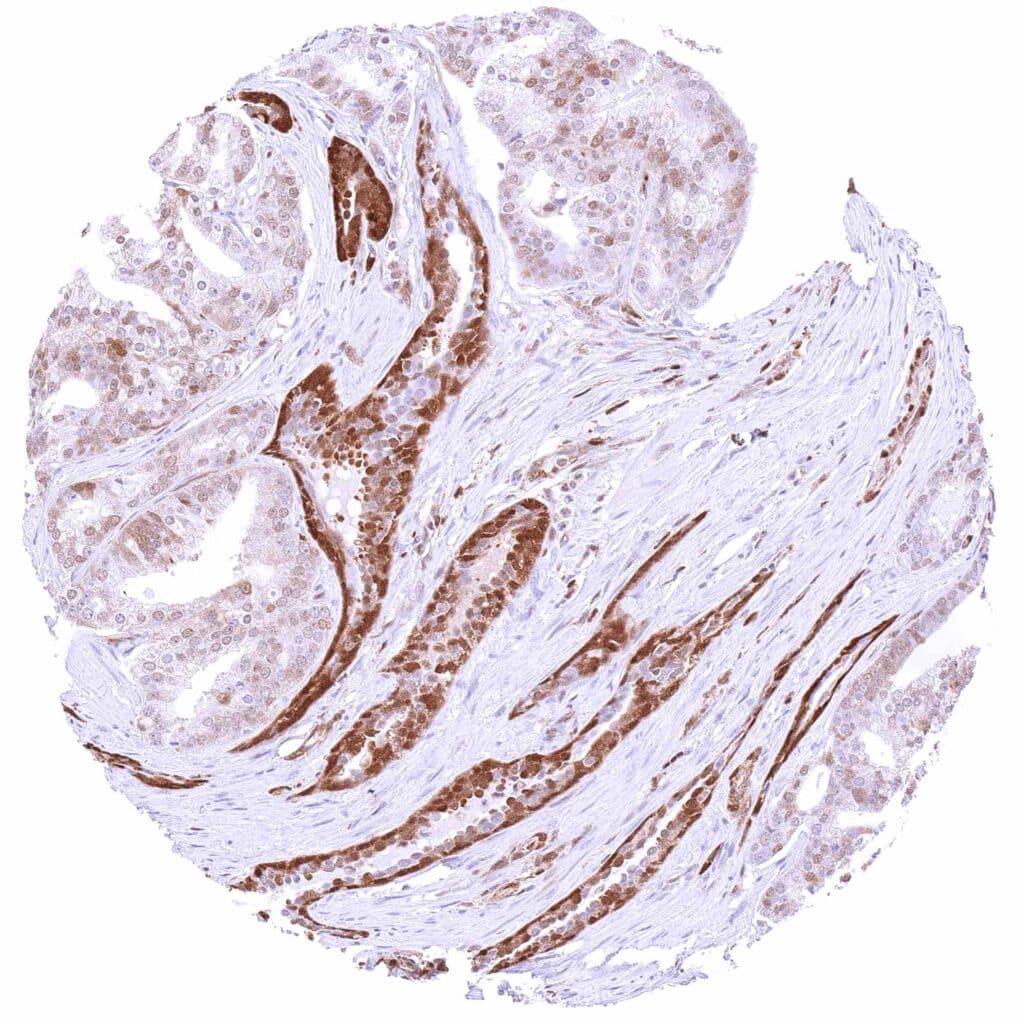

Vulva – Squamous cell carcinoma with a variable, weak to strong, predominantly cytoplasmic p27 positivity of tumor cells.